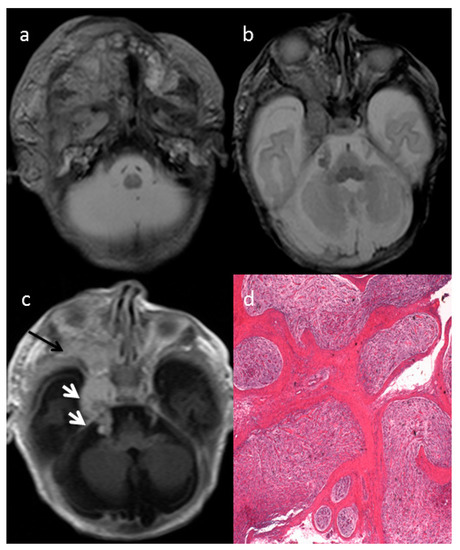

The axial T2-weighted (T2W) sequences on MRI showed an ill-defined giant cervical and facial mass of the right side (Figure 1a), infiltrating the deep spaces of the neck, showing infra-temporal fossa and intra-orbital extension (Figure 1b) and parotid gland infiltration (Figure 1a). The intracranial extension into the skull base followed the course of the right trigeminal nerve (Figure 1c, white arrows). The mass involved the deep regional soft tissues and invaded the surrounding structures, determining a proptosis of the right eye due to right side orbital enlargement. The solid part of the extensive mass was characterized by intermediate to high signal intensity on T2 and intermediate to low signal intensity on non-enhanced T1w with enhancement after gadolinium injection (Figure 1a–c). The optic nerve and extra-ocular muscles were involved by the mass. The typical MRI target-sign, namely central hypointensity with peripheral hyperintensity on T2 weighted images, was suggestive for the diagnosis of plexiform neurofibroma (PN).

The histologic examination after mass biopsy revealed diffuse nerve fascicles distension caused by a proliferation of spindle-shaped cells embedded in myxoid matrix (hematoxylin-eosin (EE), 2.5×) consistent with plexiform neurofibroma (PN) (Figure 1d).

Figure 1. The axial T2-w (a,b) and T1-w (c) of the MRI showed an ill-defined giant cervical and facial mass of the right side on the neck deep spaces with infra-temporal fossa and intra-orbital extension and parotid gland infiltration. The intracranial extension followed the course of the right trigeminal nerve ((c) white arrows). The mass involved the deep regional soft tissues causing a proptosis of the right eye ((c) black arrow). The optic nerve and extra-ocular muscles were involved by the mass (b,c). The histologic examination after mass biopsy revealed diffuse nerve fascicles distension caused by a proliferation of spindle-shaped cells embedded in myxoid matrix (hematoxylin-eosin (EE), 2.5×) consistent with plexiform neurofibroma (PN) (d).